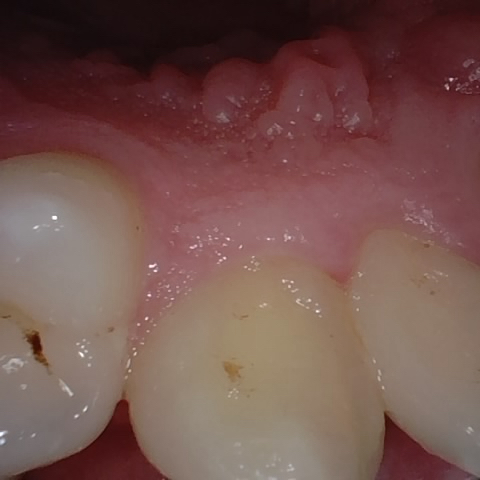

Image 72 / 2000

NHD39969

Annotated as "Good"

Original Image Rendering Image